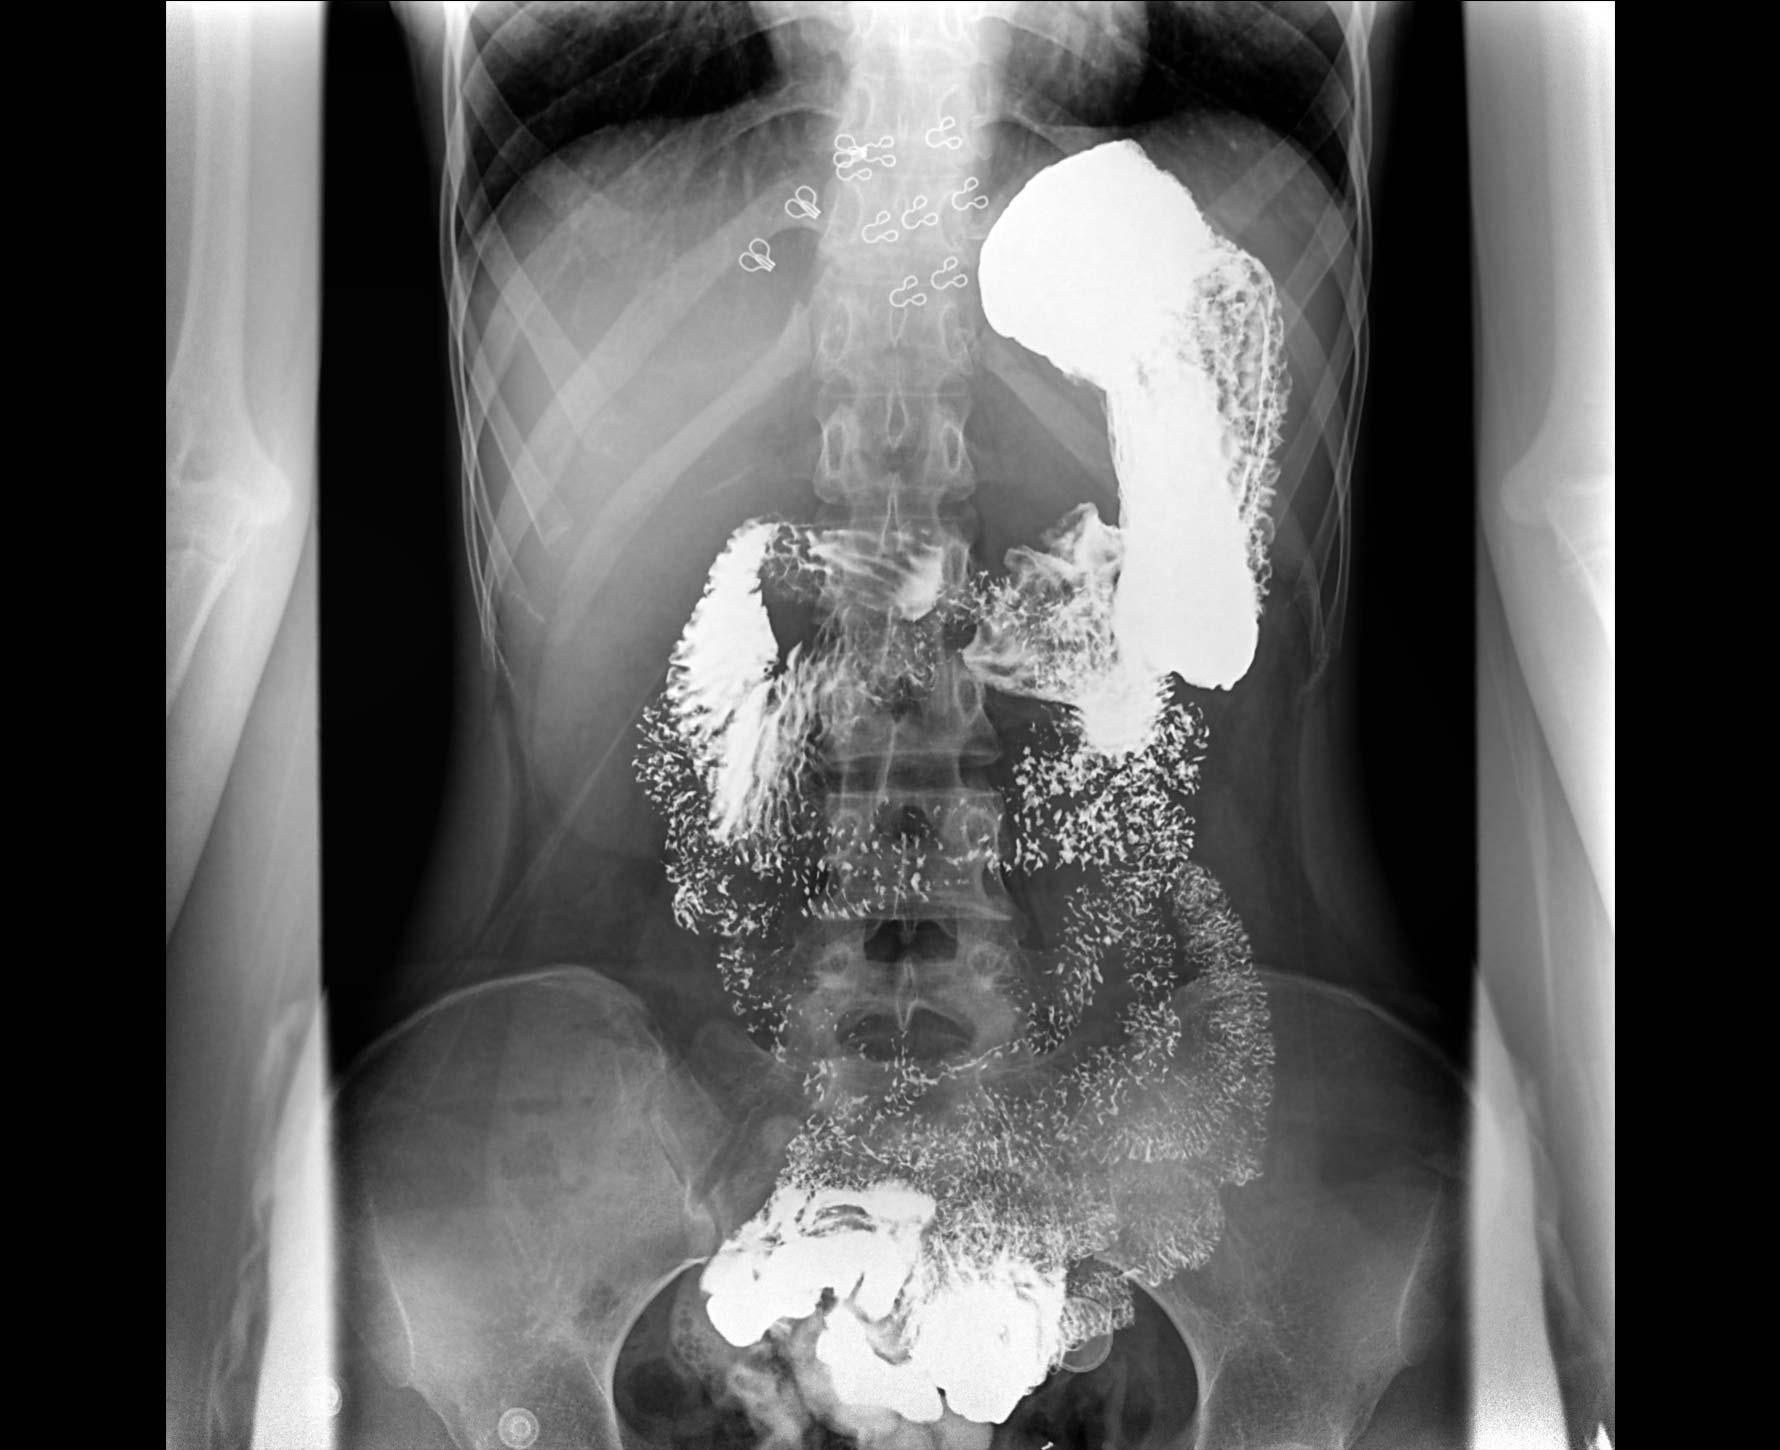

适用于各种普通

及特殊胃肠造影检查

对胃肠造影检查影像实时保存,多次回放以便确定病灶部位,患者确诊好帮手,减少漏诊。